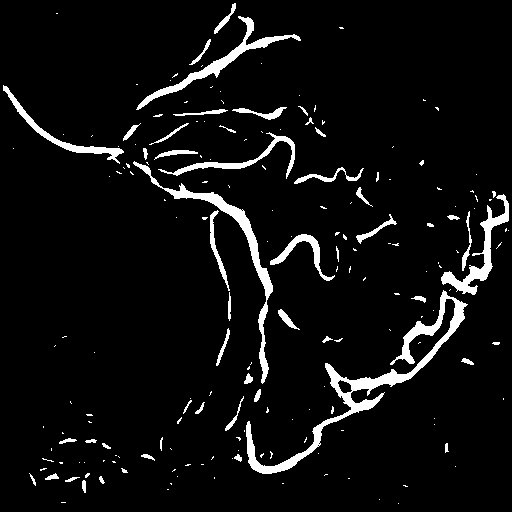

| Image | Ground truth | Video frame | Ground truth | Video frame | Ground truth |

| XCAD [33] | CADICA [19] | Our XACV dataset | |||

4.1 XACV Dataset

We collect 111 complete records of coronary artery X-ray videos, encompassing the injection, flow through the blood vessels around the heart, and dissipation of the contrast agent. Subsequently, we establish the XACV (X-ray Angiography Coronary Video) dataset. Each video consists of varying numbers of high-resolution coronary artery X-ray images. We invite experienced radiologists to annotate the vascular regions, focusing on one or two frames where the contrast agent is most prominent in each video. The XCAD dataset contains only a single image, and the CADICA video dataset does not provide corresponding ground truth. Therefore, in the following experiments, we conduct all the analyses on our collected XACV dataset and the corresponding GT for each sequence. In Figure 5, we show that compared to other publicly available datasets, XCAD [33] and CADICA [19], our dataset exhibits finer annotations in the vascular regions, providing an advantage for future related tasks. The development and use of our dataset have been approved by our institution’s IRB.